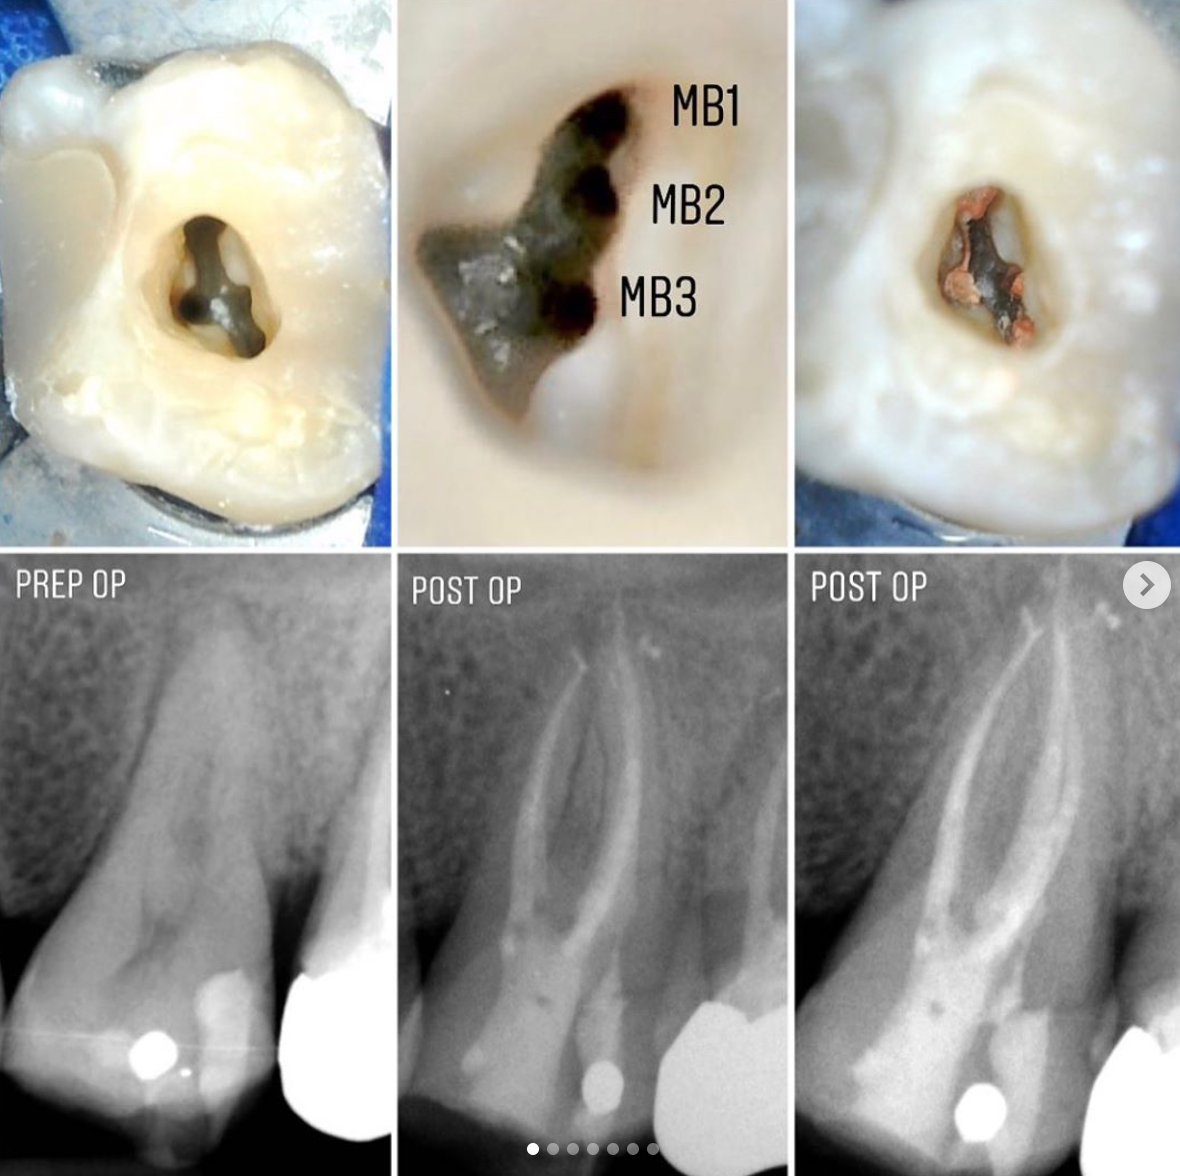

We have use of a microscope for all of our specialist endodontic cases, along with the latest technology and materials for treatment. Patient’s will be seen by our experienced endodontist, Dr Vishal Klaire. Below are some examples of Dr Klaire’s excellent work.